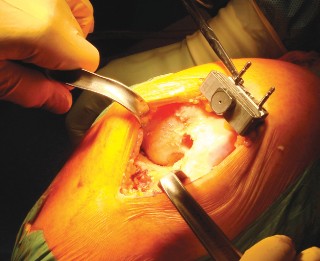

الخطوة 3: قطع عظم الساق (Tibial Cut)

- الدليل خارج النخاع (Extramedullary Guide): يُستخدم دليل خارج النخاع لقطع عظم الساق.

- إزالة الرباط الصليبي الأمامي (ACL): يتم قطع الرباط الصليبي الأمامي من موضع ارتباطه.

- تحريك الساق للأمام: تُحرك الساق للأمام (subluxed) لزيادة كشف الجزء العلوي من عظم الساق.

- وضع الدليل: يُوضع الدليل خارج النخاع فوق الثلث الإنسي من الحدبة الظنبوبية، بمحاذاة عرف الساق، وفي مركز مفصل الكاحل.

- تحديد الميل: يُحدد الميل المناسب ويُثبت الدليل في مكانه.

- القطع والحماية: تُحمى الأربطة الجانبية بالمبعدات، ويُقطع عظم الساق بشكل عمودي على محوره.

اعتبارات هامة (Pitfalls):

- يجب تجنب القطع المائل لعظم الساق (varus cut) بأي ثمن. يرتبط القطع المائل لعظم الساق في أي عملية استبدال مفصل الركبة بزيادة معدلات الفشل، خاصة في المرضى الذين يعانون من السمنة المفرطة. يحرص الأستاذ الدكتور محمد هطيف على الدقة القصوى لتجنب هذا الخطر.

الخطوة 4: إكمال قطع عظم الفخذ وتحديد الحجم

- نظام التوجيه الخلفي: يُستخدم نظام توجيه خلفي لإكمال قطع عظم الفخذ.

- تحديد الدوران الخارجي: يُحدد المقدار الصحيح للدوران الخارجي لعظم الفخذ بناءً على المحور اللقمي الخلفي، والمحور فوق اللقمتين، وزاوية 90 درجة بالنسبة لمحور الساق (السطح المقطوع)، والمحور الأمامي الخلفي (خط وايتسايد).

- تحديد الحجم: يُوضع الدليل على الجزء البعيد من عظم الفخذ، ويُحدد حجم عظم الفخذ، ويُختار الحجم المطابق للمريض.